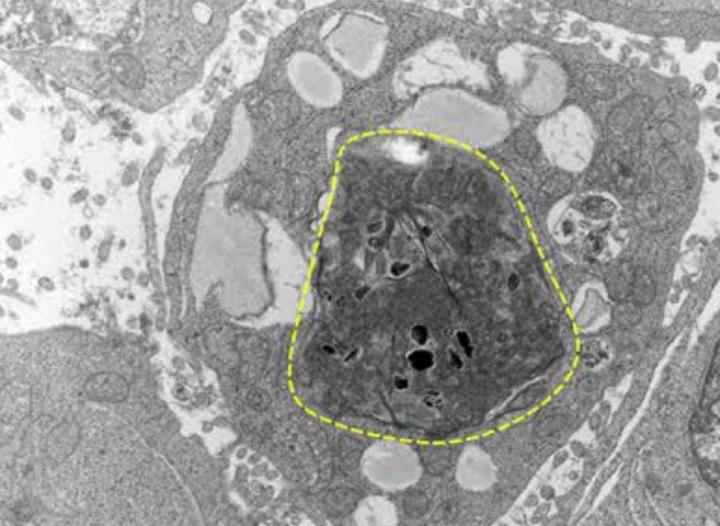

In their study, published in the January issue of the Journal of Experimental Medicine , the researchers describe how chemotherapy or other targeted therapies create a build-up of tumor cell debris, comprised of dead, fragmented cancer cells. In animal models, the team observed that this cell debris sets off an inflammatory cascade in the body and also encourages lingering, living cancer cells to develop into new tumors.

Strikingly, they saw that the co-mingling of debris and living tumors cells resulted in 100 times more accelerated tumor growth. And the culprit? A particular molecule -- named phosphatidylserine -- that appears during the cell death process that remains exposed on the dead cell fragments.

Once detected by the immune system, phosphatidylserine sets off a flood of pro-inflammatory activity, creating the perfect storm for unfettered tumor growth from cancer cells that evaded initial drugging. These tumors are then resistant to further chemotherapy.